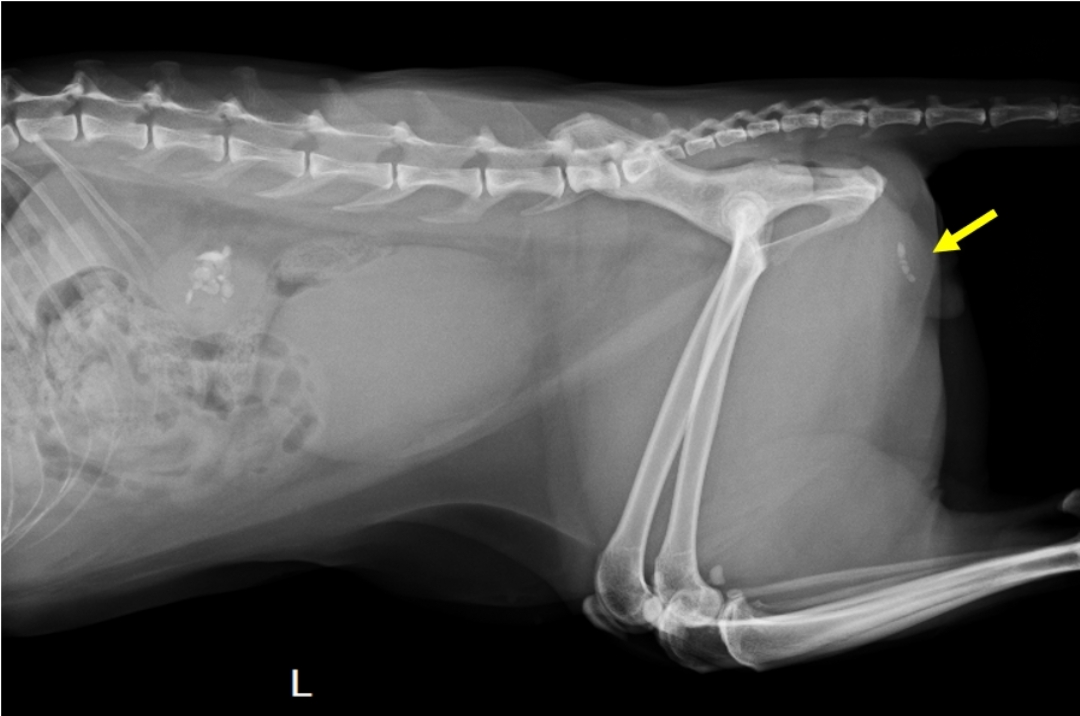

喵喵是一隻九歲已絕育的公貓,因為頻尿、排尿疼痛等症狀,於外院診斷為膀胱結石症並轉診至本院。於門診的X光片下,

可見到尿道中有四顆細小的結石(圖一)、雙側腎臟各有數顆結石,以及異常漲大的膀胱,表示結石已完全阻塞了尿路;而血檢亦顯示出腎指數上升,表示因為無法排尿,喵喵已出現了急性的腎損傷。

圖一、X光側照可見腎臟結石、漲大的膀胱,和尿道中有四顆結石。